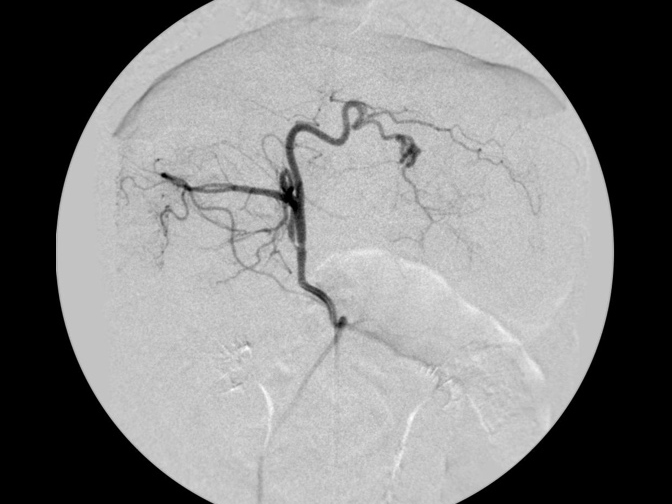

カテーテルでの造影検査